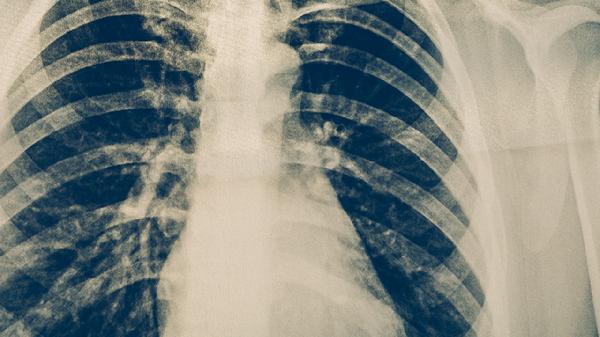

肺癌患者使用中药期间应定期复查影像学及肿瘤标志物,出现发热、咯血加重等情况需及时就诊。饮食宜清淡富含优质蛋白,如蒸蛋羹、鲫鱼汤等,避免辛辣刺激性食物。保持适度有氧运动如八段锦、散步等,但避免过度劳累。心理疏导与家庭支持对改善预后有重要作用,建议参与抗癌社团活动。